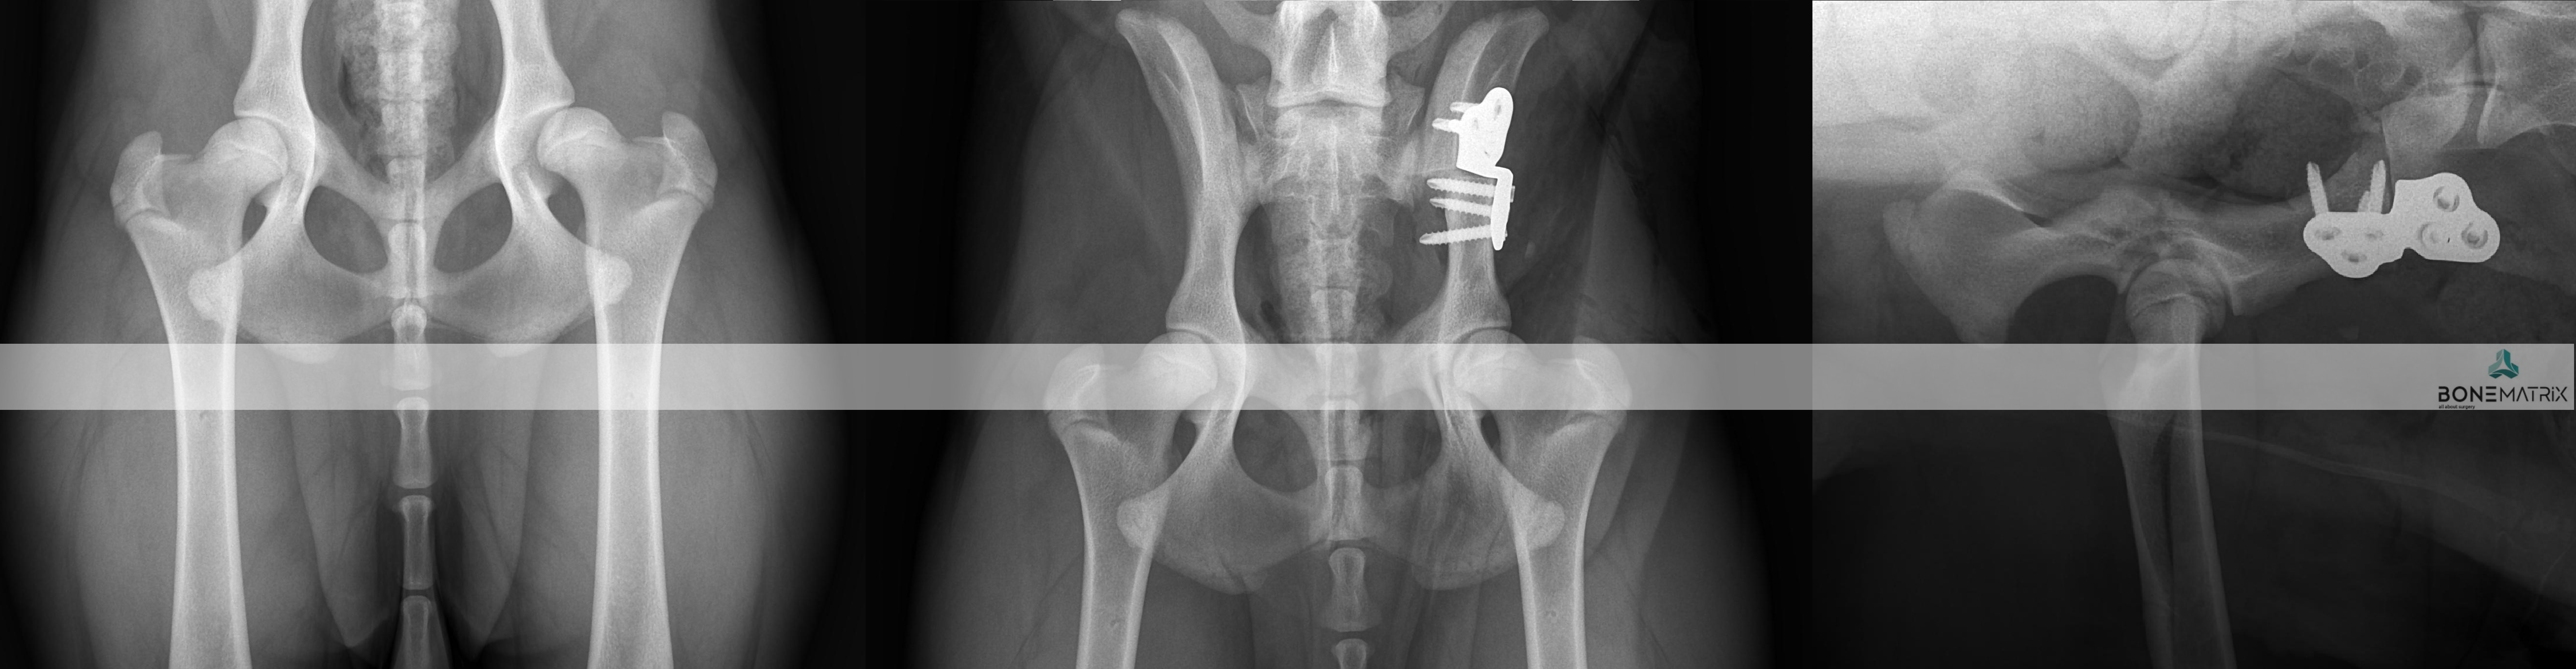

DPO (double pelvic osteotomy) é um procedimento preventivo realizado em pacientes onde o despiste de displasia de anca prevê o desenvolvimento desta doença.

Inicialmente deve ser realizado um despiste de displasia de anca com recurso a um estudo radiográfico especifico para que o paciente seja avaliado e seja definido como um bom candidato à aplicação desta técnica.

O que é?

A DPO consiste na realização de dois cortes ao nível da pélvis que permitem a rotação do fragmento criado. Este fragmento inclui a porção articular da pélvis, na articulação coxofemoral (o acetábulo).

Ao rodar este fragmento conseguimos uma maior cobertura da cabeça femoral pelo acetábulo, impedindo o movimento de saída da cabeça femoral de dentro do acetábulo. Ao impedir este movimento (laxitude articular) impedimos o desenvolvimento de lesões de osteoartrite provocada por ele, e desta forma impedimos o desenvolvimento da doença de displasia de anca.

Após rotação do fragmento, este é estabilizado na posição pretendida com recurso a placas bloqueadas especializadas para a realização desta cirurgia, garantindo assim a cicatrização do osso no ângulo previamente definido.

Este procedimento pode ser realizado bilateralmente no mesmo momento cirúrgico.

Quem são os bons candidatos para realização de DPO?

Este procedimento deve ser realizado idealmente aos 5.5 meses daí aí importância dos despiste de displasia de anca serem realizados muito cedo na vida do animal.

Os pontos essenciais que definem um bom candidato são a idade do paciente, desenvolvimento mínimo de osteoartrite a nível articular e presença de um sinal de Ortolani positivo (teste realizado durante a consulta pré-despiste).

Qual a taxa de sucesso esperada?

Após a realização desta cirurgia a claudicação irá resolver-se por norma em 3 meses após a cirurgia.

A taxa de sucesso de aplicação desta técnica é de cerca de 90% onde os paciente apresentam desde uma melhoria significativa até ao retorno à condição normal. Em alguns casos podem ser desenvolvidas alterações de osteoartrite ligeiras, mas por norma não são suficientes para provocar claudicação até que o paciente seja geriátrico.

Este procedimento preventivo é preferido a outras técnicas similares como a TPO por resultar num pós cirúrgico menos doloroso por comparação.

Que complicações podem surgir?